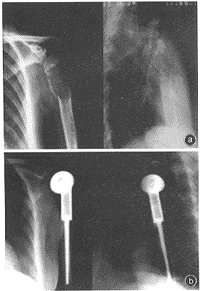

a左肱骨近端骨巨细胞瘤伴病理性骨折术前b肿瘤

切除、人工肱骨头置换术后17年,人工肱骨头固定牢靠

图2左肱骨近端骨巨细胞瘤伴病理性骨折